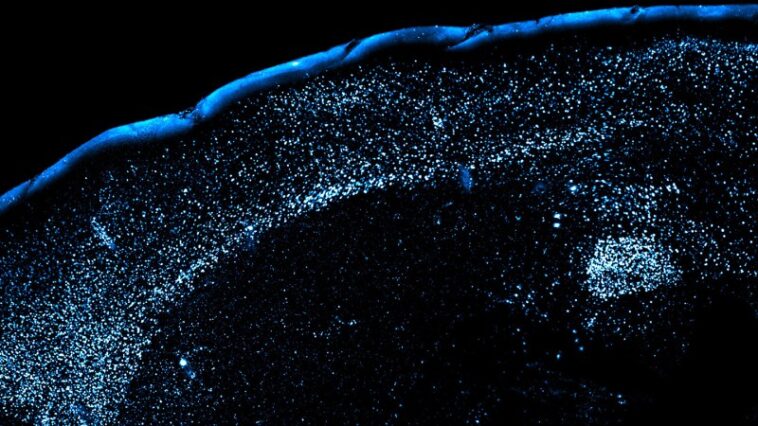

L'équipe a fait boire du raisin de raisin Kool-Aid et, 30 minutes plus tard, a injecté les rongeurs avec du chlorure de lithium pour les rendre malades. Deux jours plus tard, ils ont de nouveau donné à la souris le raisin Kool-Aid. L'équipe a effectué de nombreuses variations sur cette expérience simple et a jeté un coup d'œil à l'intérieur du cerveau de la souris à chaque étape. Dans certaines expériences, les chercheurs ont euthanasié des souris et ont rendu leur cerveau transparent pour les imaginer en 3D. Dans d'autres, les chercheurs de souris génétiquement modifiées afin que leurs neurones CGRP puissent être allumés et éteints en utilisant de minuscules électrodes légères pour suivre l'activité des petites taches de l'amygdale pendant que les souris étaient vivantes.

Lorsque les souris sont tombées malades après avoir bu pour la première fois du raisin de raisin, leurs neurones CGRP ont réactivé et composé la sensibilité des neurones de l'amygdale qui représentaient la saveur. Ces mêmes neurones ont réactivé lorsque les souris ont rencontré à nouveau le raisin Kool-Aid plus tard, suggérant que le renforcement des neurones CGRP aide l'amygdale à se souvenir des aliments dangereux. Cet effet ne s'est pas produit chez la souris qui avait goûté au raisin kool-aid sans tomber malade; Seules les expositions pour la première fois ont laissé une impression durable. Chez l'homme, la nouveauté qui nous induit à nous rappeler l'intoxication alimentaire pourrait être un peu plus complexe que le goût seul: un mélange d'épices, un nouveau restaurant ou tout autre élément inconnu d'une expérience alimentaire peut nous sortir.